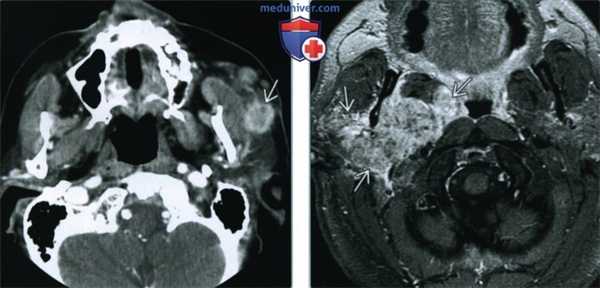

(Слева) MPT Т2ВИ FS с КУ, аксиальная проекция. Ранее пациенту выполнялось удаление доброкачественной смешанной опухоли правой околоушной железы. Нa изображениях визуализируется типичная картина рецидива опухоли - множественные гиперинтенсивные новообразования, напоминающие «гроздья винограда».

(Справа) УЗИ в продольной плоскости у пациента, ранее оперированного по поводу доброкачественной смешанной опухоли. В месте операции определяется скопление солидных гипоэхогенных узлов. Множественные доброкачественные смешанные опухоли сами по себе возникают редко (

(Слева) МРТ Т1ВИ FS с КУ, аксиальная проекция. В области шилонижнечелюстного тоннеля визуализируется агрессивное новообразование, прорастающее в сосцевидный отросток. Подобный внешний вид характерен для любой агрессивной злокачественной опухоли околоушной железы. Гистологически - миоэпителиальная карцинома из доброкачественной смешанной опухоли.

(Справа) КТ с КУ, аксиальная проекция. Визуализируется образование, неравномерно накапливающее контраст, заполненное кальцификатами неправильной формы; его центр находится в хвосте околоушной железы. И хотя в доброкачественной смешанной опухоли тоже могут появляться кальцификаты, в этом случае был выставлен диагноз хондросаркомы из доброкачественной смешанной опухоли.

(Слева) КТ с КУ, аксиальная проекция. В добавочной доле околоушной железы визуализируется инфильтративная опухоль с нечеткими контурами. Опухоль оказалась протоковым раком, наиболее распространенным злокачественным новообразованием, происходящим из доброкачественной смешанной опухоли.

(Справа) МРТ Т1ВИ FS с КУ. Околоушная железа замещена агрессивной опухолью, неравномерно накапливающей контрастное вещество. Гистологическое исследование: истинная злокачественная смешанная опухоль, в препарате определялись участки карциномы, саркомы и остатки простой доброкачественной смешанной опухоли.